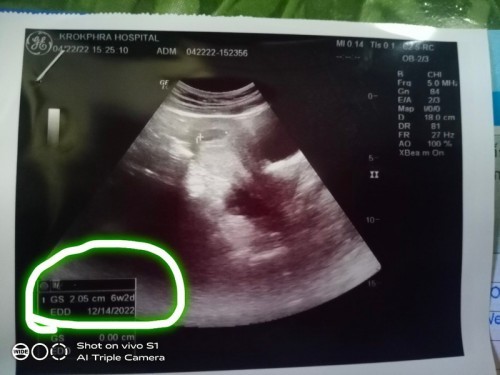

ขอสอบถามค่ะ เราไปซาวมา6w2dถุงตั้งครรภ์2.05ปกติไหมคะ รึเราดูผิด

ขนาดถุงตั้งครรภ์จะเปนตัวบอกว่ากี่วีคค่ะ แต่ถ้าเจอตัวเด็กแล้วจะวัดขนาดจากตัวเด็กเป็นหลัก